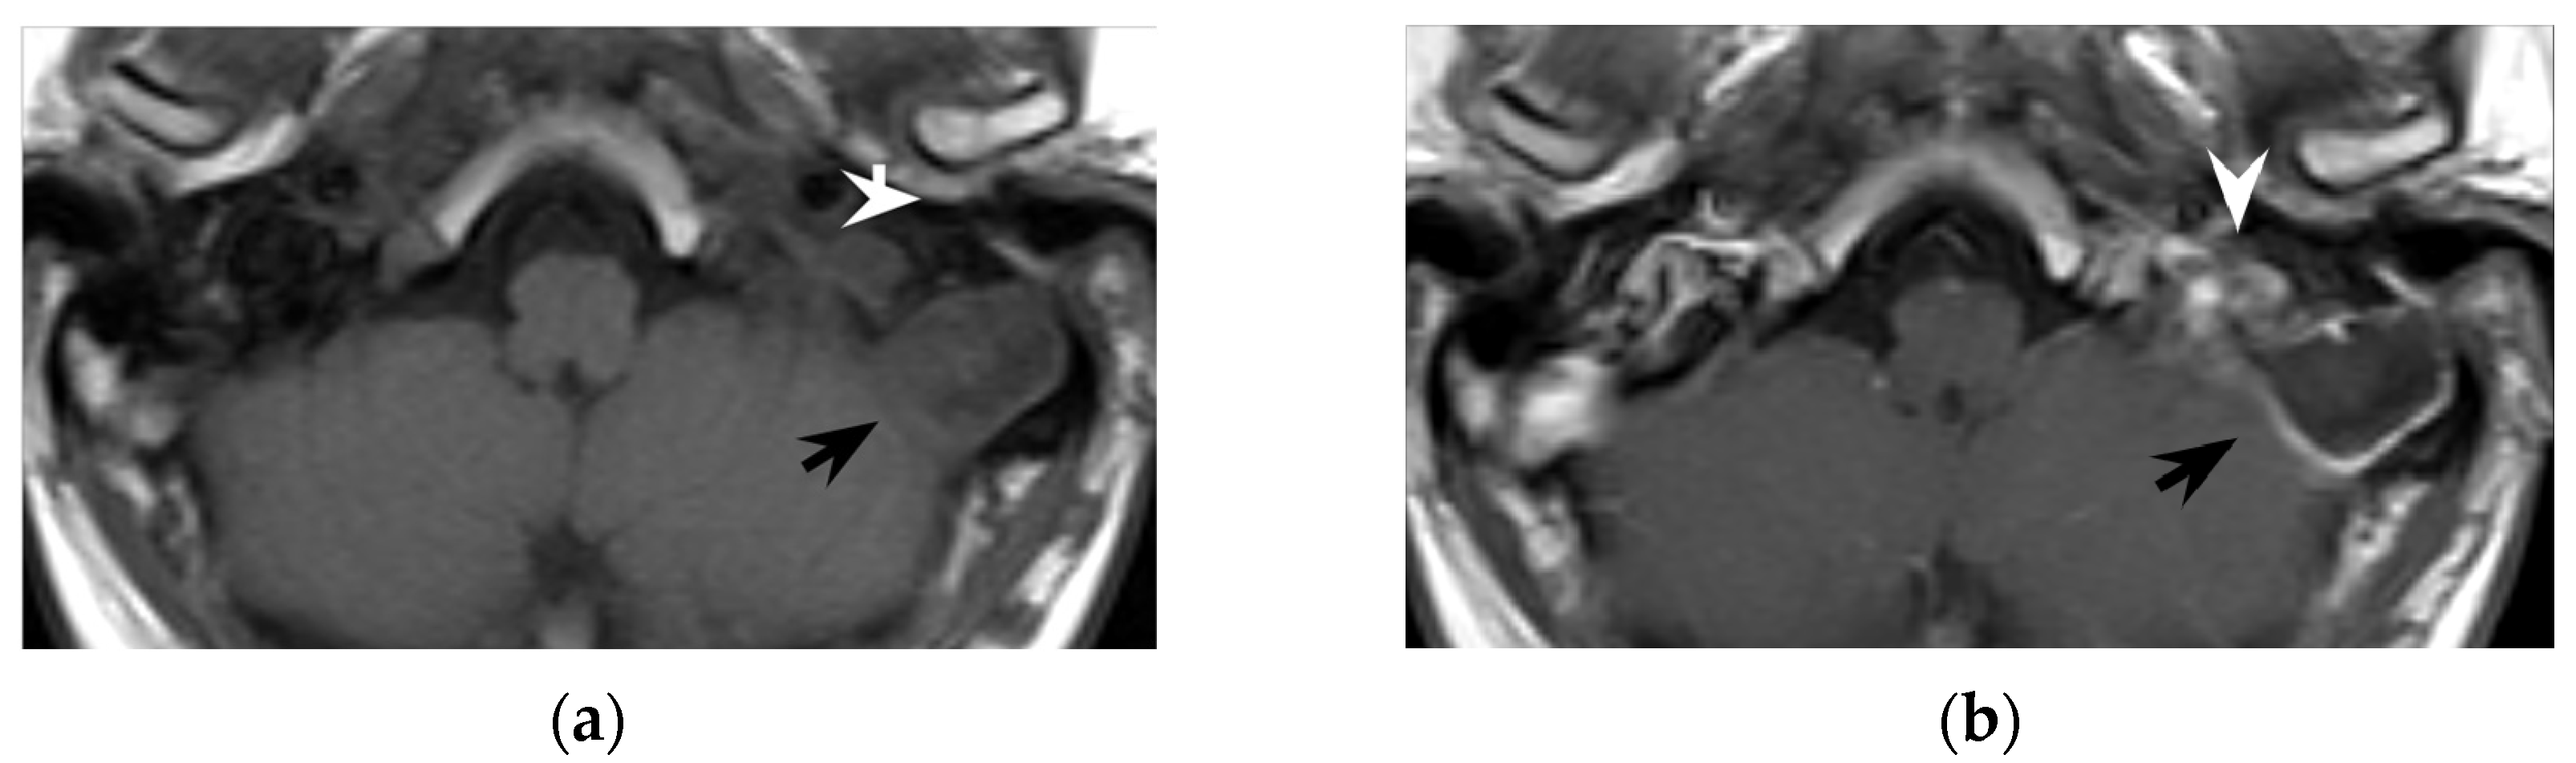

However, despite its crucial pathogenic role for the suppurative path, bone defects in the mastoid tip have been precisely outlined only in around half of all literature reports (51/97 patients, 53%). Indeed, in 7/97 patients (7%) the mastoid tip was considered intact, revealing that the diagnosis of Bezold’s abscess can be achieved even without overt bone erosion, especially in younger children (3/7 patients were younger than 5 years old). The incomplete pneumatization of mastoid cells before the age of five is well known and is supposed to hinder the diffusion of the suppurative process across the thickened mastoid bone wall. Before the age of five, more destructive infectious processes or emissary vein bone canals likely allow Bezold’s abscess occurrence [8]. A recent case of a woman affected by Goldenhar syndrome with an unremarkable mastoid bone (Figure 5) highlighted those atypical origins of Bezold’s abscess that should be accurately investigated in syndromic patients [15].

Figure 5. Thirty-year-old woman with oculo-auricular-vertebral spectrum. Contrast-enhanced axial CT (a) shows hypodense left neck abscess in the parapharyngeal and pharyngeal mucosal spaces, with minor involvement of the visceral and posterior cervical space (dotted rectangle). Note the peripheral enhancement and the soft tissue oedema. Axial CT with bone kernel (b) shows hypodense cholesteatoma eroding the os tympanicum (black arrow) as the origin of the neck abscess. Coronal T2w MRI (c) shows an hyperintense neck collection (white arrow) medial to the sternocleidomastoid muscle (white arrowhead). The patient proved to have a Bezold’s abscess associated with an os tympanicum cholesteatoma.